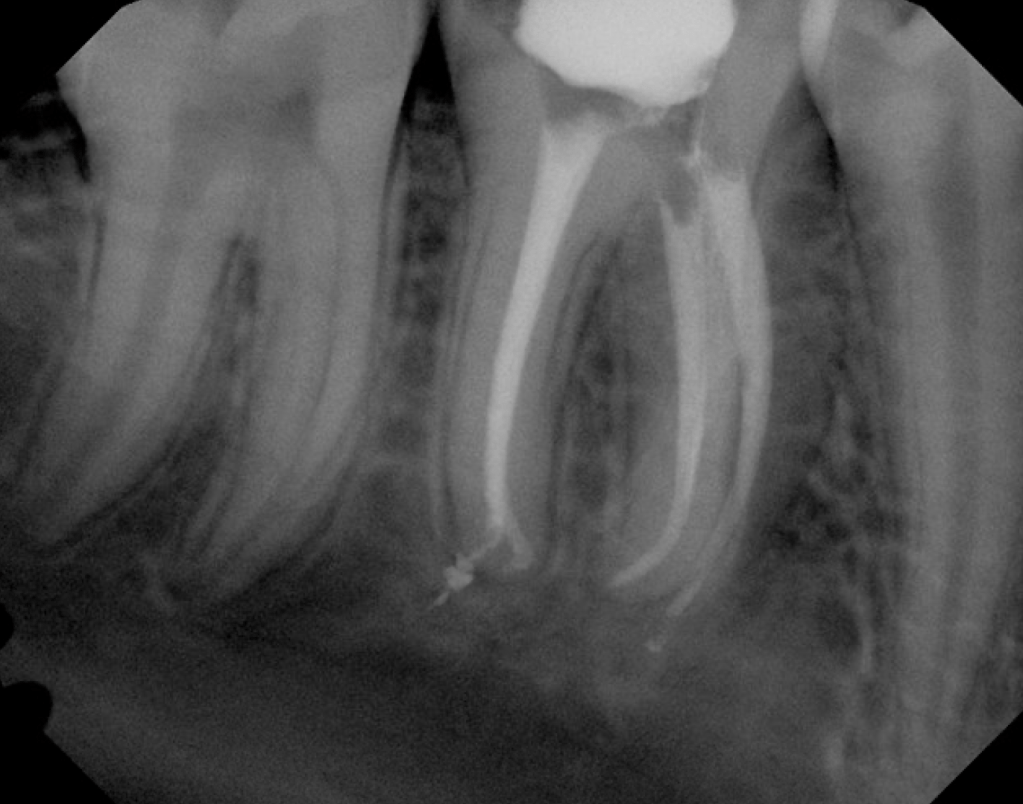

#18 NS-RCT